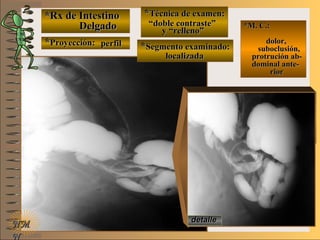

*Rx de Estómago*Rx de Estómago

**Proyección:Proyección:

**Técnica de examen:Técnica de examen:

A-A-

B-B-

C-C-